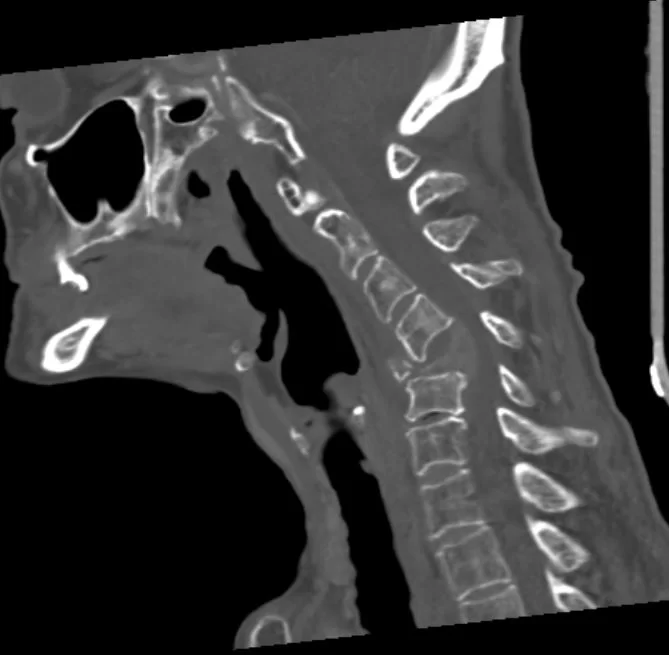

Ασθενής γυναίκα 61 ετών με σημαντική τετραπάρεση (αδυναμία άνω & κάτω άκρων) λόγω νεοδιαγνωσθείσας χωροκατακτητικής εξεργασίας (όγκος) στον Α5 σπόνδυλο, ο οποίος έχει διαβρώσει πλήρως το οστό και έχει προκαλέσει κάταγμα του σπονδύλου με αποτέλεσμα πίεση του νωτιαίου μυελού και σημαντική παραμόρφωση της σπονδυλικής στήλης.

Προεγχειρητικές Εικόνες (Μαγνητική Τομογραφία & Αξονική Τομογραφία)